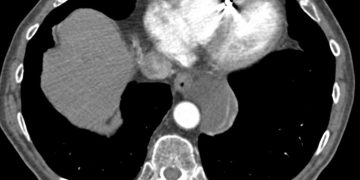

Yemek Borusu Duplikasyonu, gerçek yemek borusu yanında ve onunla ilişkili kistik tüp şeklinde ki yapının oluşması durumudur. İçersinde hücresel atıklar ...